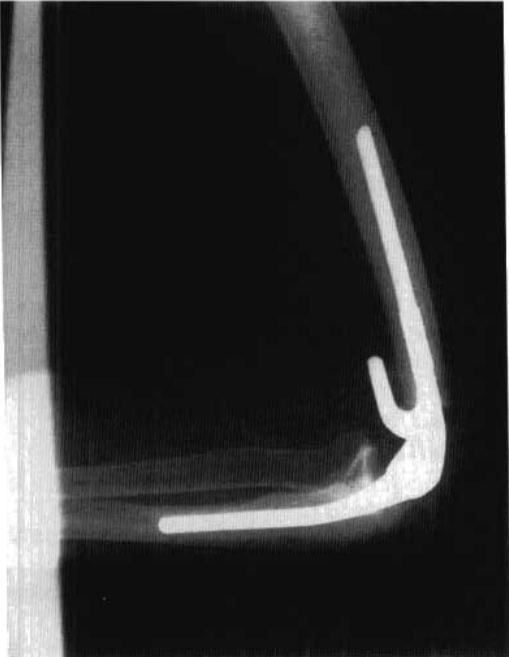

Изучение анатомии: поперечный диаметр дистального эпифиза плеча